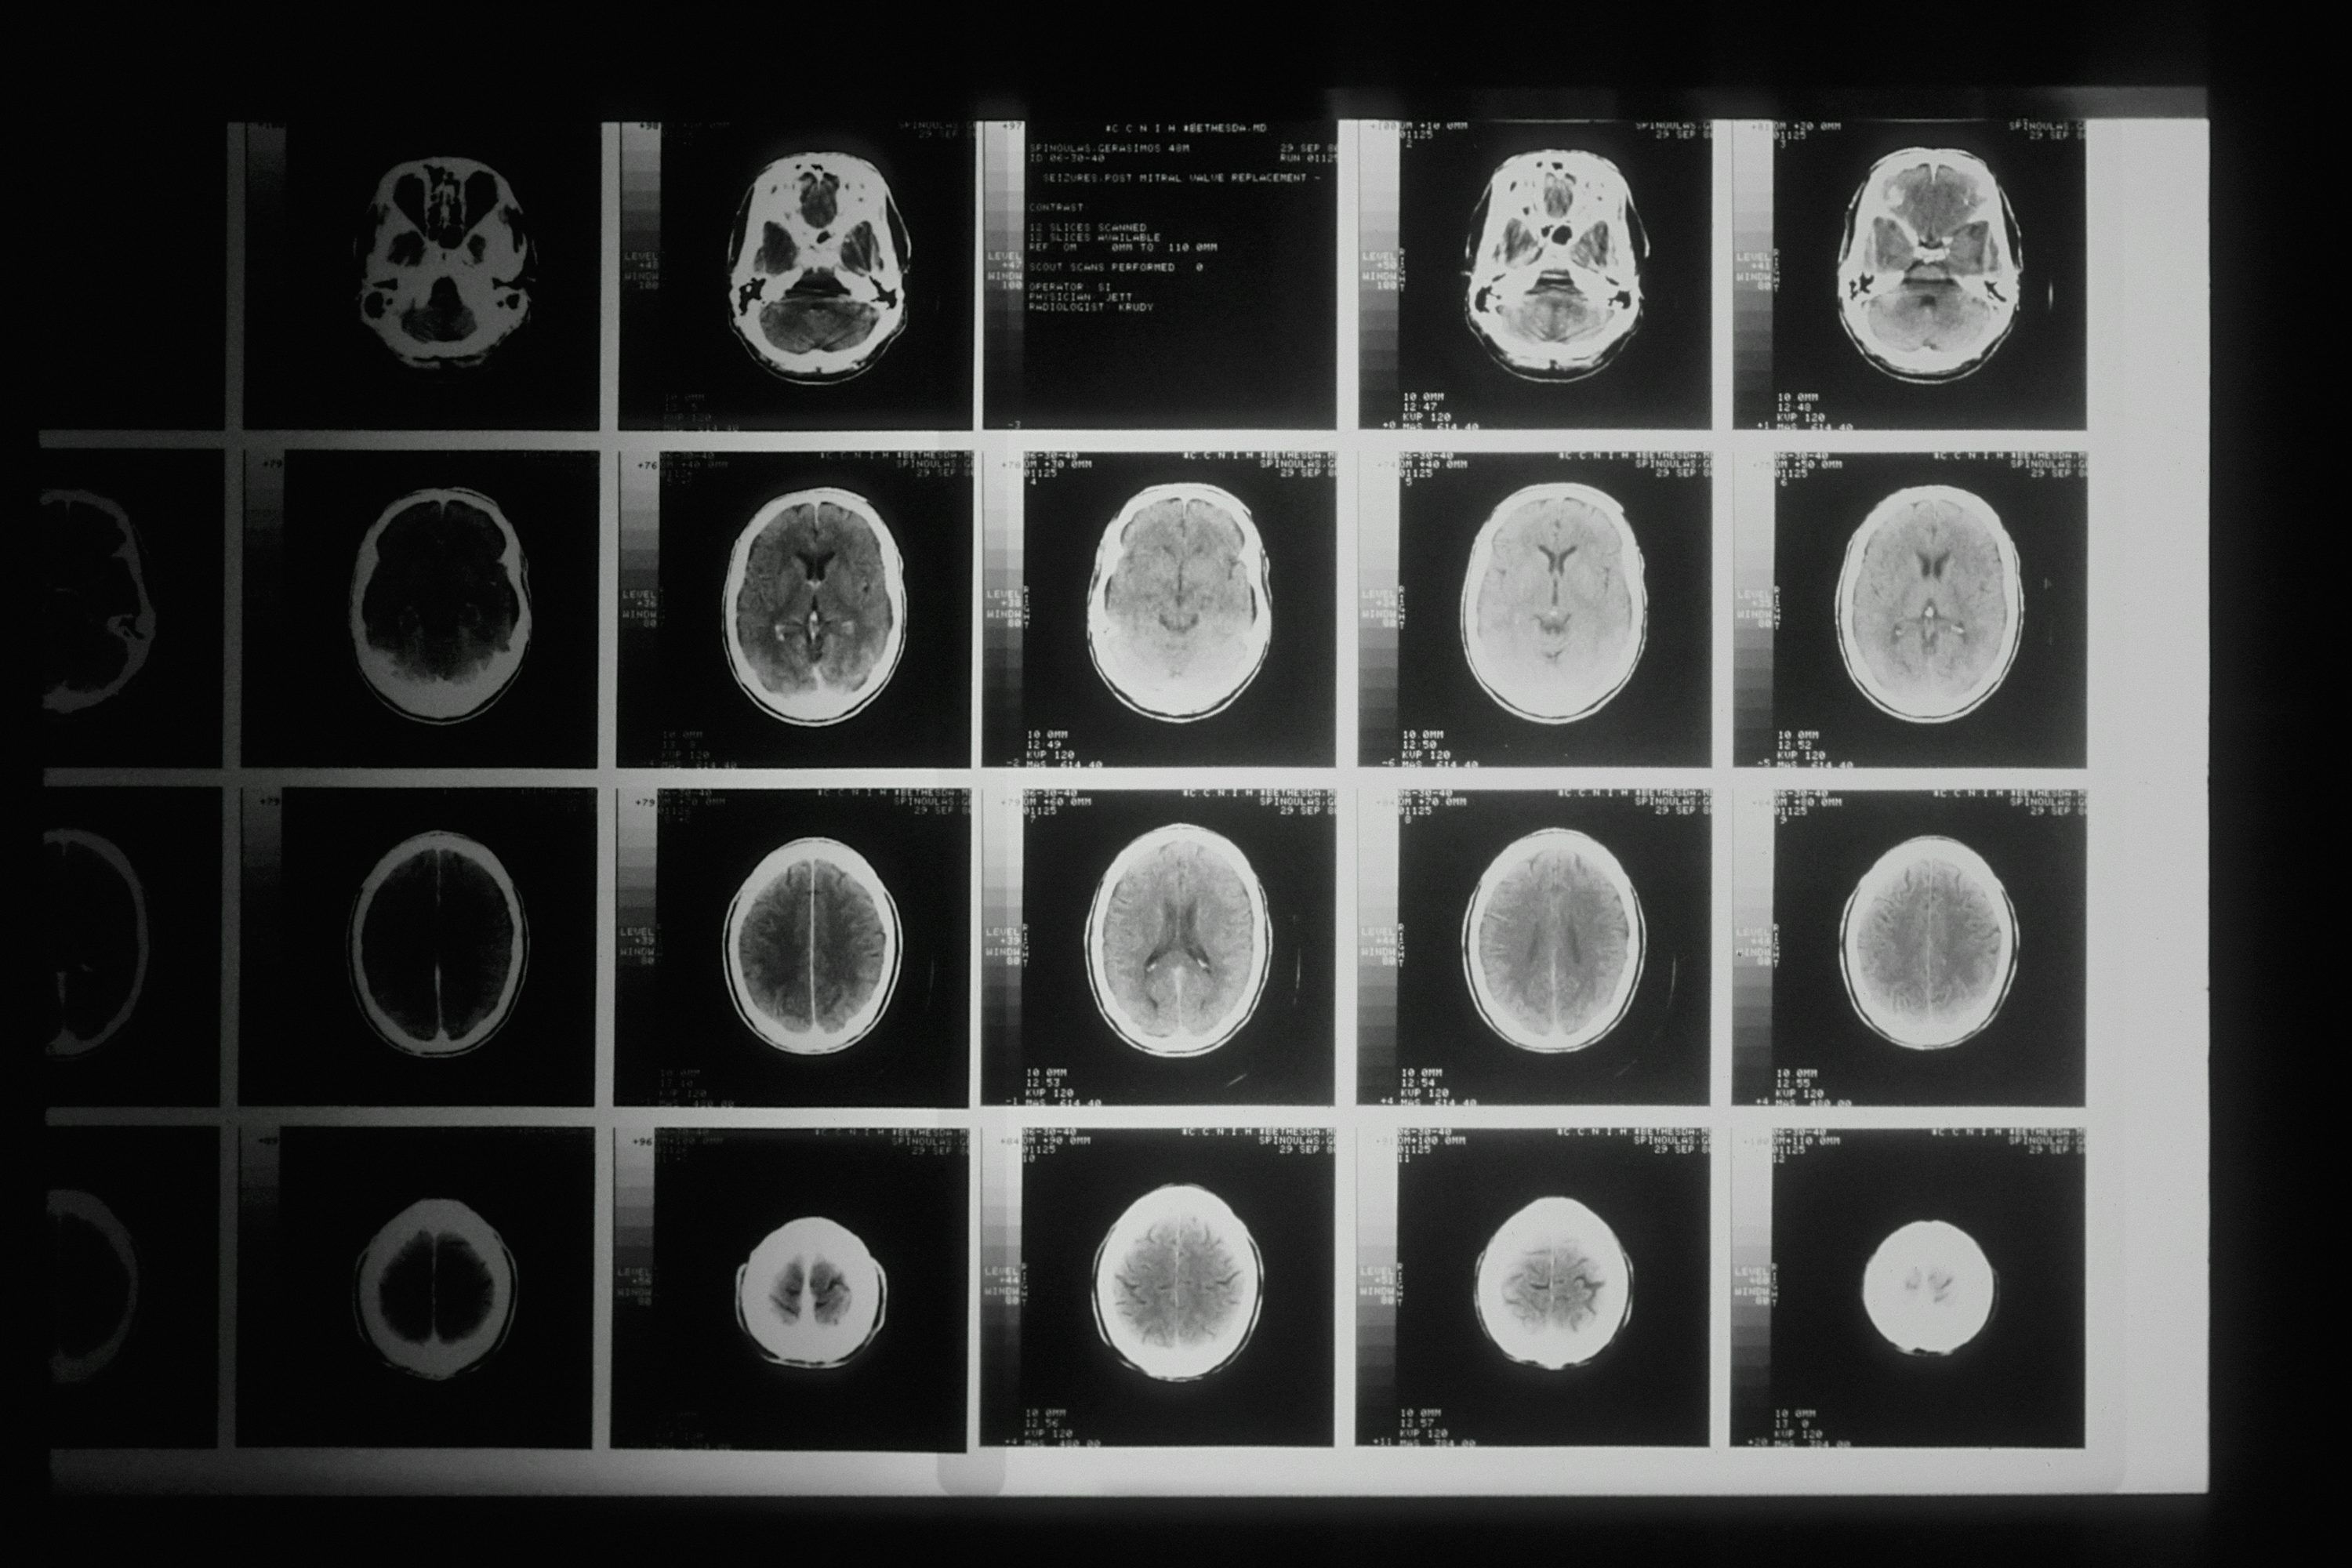

Q2. 뇌경색과 뇌출혈 초기증상은 어떻게 다른가요?

A. 두 질환의 초기증상은 매우 유사하여 증상만으로는 구별이 거의 불가능합니다. 다만 뇌출혈은 갑작스러운 극심한 두통, 구토, 의식 저하가 더 흔하고, 증상이 더 급격하게 악화되는 경향이 있습니다. 하지만 정확한 진단은 병원에서 CT나 MRI 검사를 통해서만 가능하므로, 증상이 나타나면 즉시 응급실로 가야 합니다.